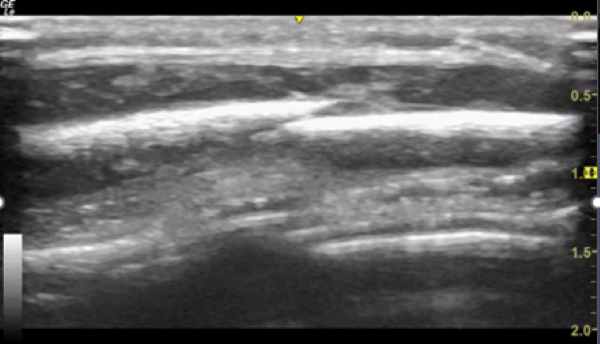

Figure 1. POCUS of parietal skull showing fracture

Figure 2 Additional image of parietal skull fracture

You explain to the parents that these images are consistent with a skull fracture and ask how this may have happened in a child not yet independently mobile.

The periosteum is viewed as a solid hyperechoic line. As you look further intracranially, you may see the various layers surrounding the brain cortex, although the pia mater is usually difficult to visualise.

- If there is a fracture, this is seen as a disruption periosteal layer, ie, the hyperechoic line. Follow this region in both transverse and longitudinal planes assessing its extent.

- In the setting of a fracture, there is likely to be an obvious haemorrhage within the skin and connective tissues. There may also be an associated extradural or subdural haematoma.